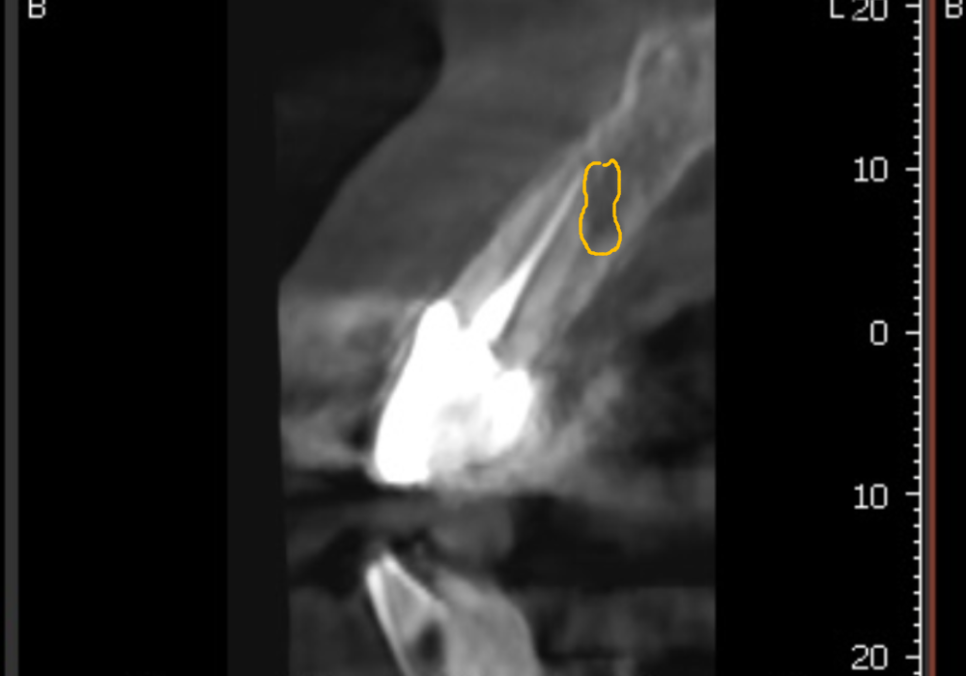

탐침 기구로 체크해 보니,

보철 안쪽으로 기구가 완전히 통과될 정도로

내부 공간이 벌어져 있었는데요~

방사선 사진을 살펴보니 역시나,

2차 충치로 인해 치아 뿌리와 보철물 사이가

완전히 끊어져있네요.. ㅜㅜ